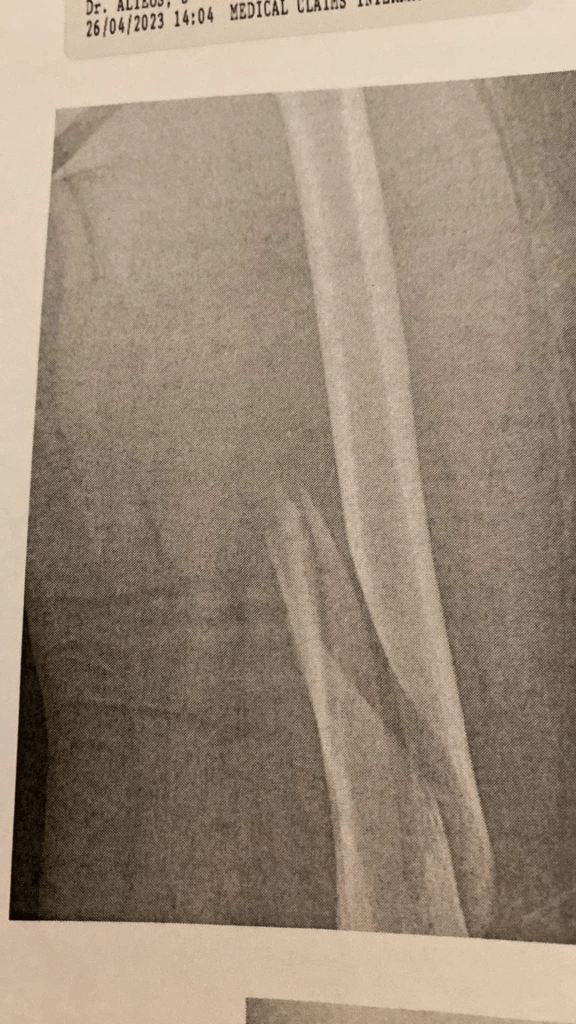

They take me for X-rays and return me to the big room. I meet the trauma doctor in charge, Dr. Moreno. He’s in his late 30s, with dark hair and eyes, a kind manner, and he speaks English, unlike everyone else I’ve encountered in the ER. He tells me my femur is badly fractured and I need surgery. But not in his hospital. They wouldn’t be able to do it for a week or more. And it’s too serious for me to fly back to the US.

My Facebook posts have brought offers of help. I get a message from a woman I don’t know well, but who is a Facebook friend. Her dad is a retired orthopedist. Would I like to get a second opinion from him about my injury? Sure! I send her my x-ray. She also worked as a hospital social worker, and gives me advice about traveling home with medications. I ask her what she or her dad knows about the use of antibiotics before surgery and wait for her to respond.

The break in my femur is periprosthetic, close to the artificial knee, so he needs to know more about my prosthesis. Like who manufactured it. Something about whether it is a “rear motion” device. This means nothing to me. He gives me his email address and leaves me to ponder how I’m going to get this information. Does this mean I can’t have surgery until I find out who made my knee? OMG!

My obsessive organization comes in handy sometimes! I talk her through opening the right file drawer, locating all the medical files and finding alphabetically the one labelled “Ortho.” A scientist by training, she has no trouble reading through the medical language to find the operational report. She takes a picture and sends it to me. I forward it to Dr. de la Cuesta.

Soon I’m back in my room. I’m thrilled I’m not nauseous, my usual response to anesthesia. After a while a young man comes in to take me for x-rays, but it turns out to be comic relief. He wheels me into an elevator and to the radiology room on another floor. The first time I was here, they moved me from the hospital bed to the fixed platform in the middle of the room while I yelled that it hurt. This time it seems they don’t want to move my body. A young woman comes out of an inner office and the two of them manoeuver my bed around the room. They adjust and readjust the x-ray machine on its arm attached to the ceiling, trying to figure out how to get the pictures they want. They bump the bed up against a wall, turn it around part way, try to reposition it, bump up against another wall. It’s hilarious, but I’m not laughing. This is a modern radiology department? They finally take some pictures and return me to my room.